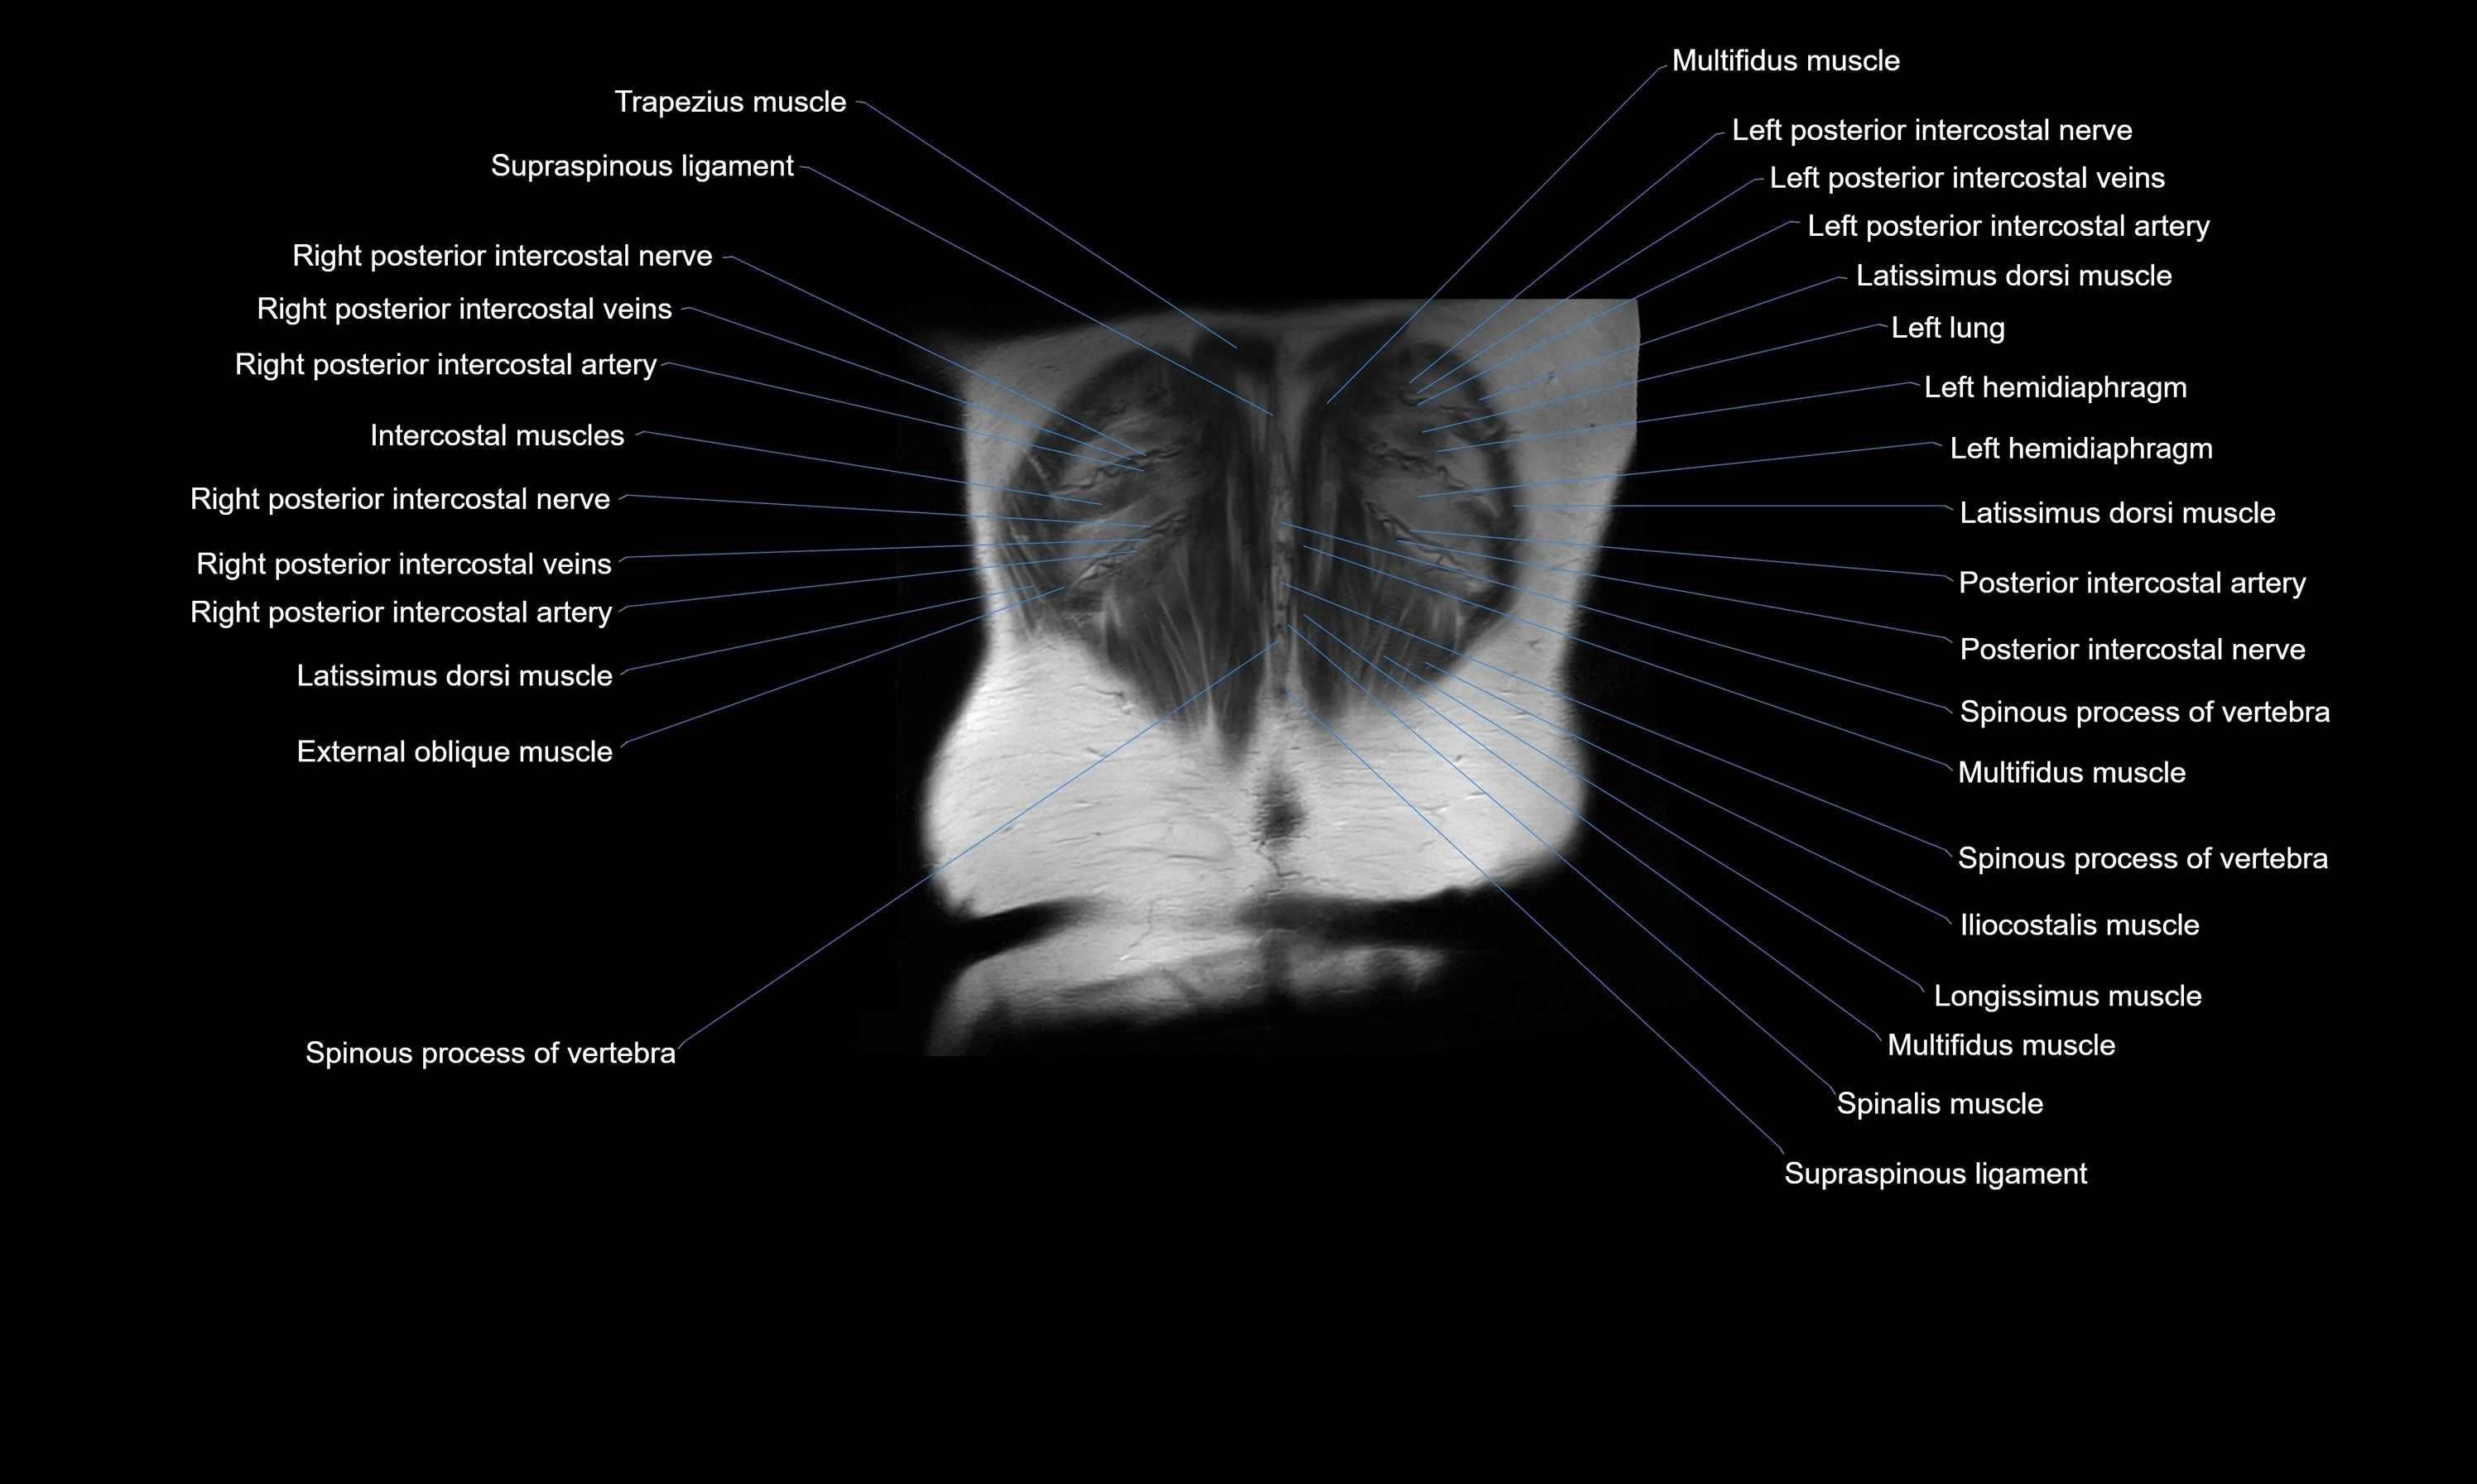

- Erector spinae muscles

- Intercostal muscles

- Latissimus dorsi muscle

- Serratus posterior inferior muscle

- Supraspinous ligament